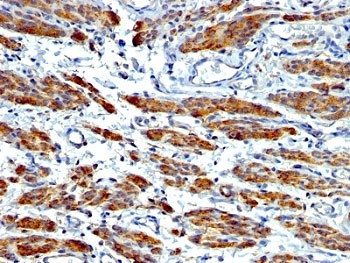

IHC: Formalin-fixed, paraffin-embedded human Leiomyosarcoma stained with SMMHC antibody (MYH11/923).